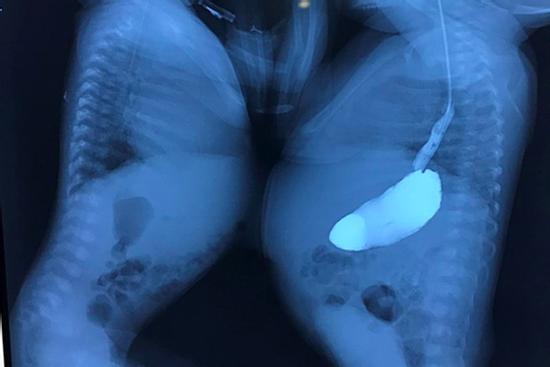

Đầu bé 1 tuổi tự nhiên to lên, bác sĩ lấy ra cả một bào thai trong não

Ca bệnh đặc biệt được công bố trên tạp chí Neurology được xác nhận là một trường hợp "thai trong thai" cực hiếm, trong đó đứa bé ra đời đã mang theo bào thai người em song sinh trong não.